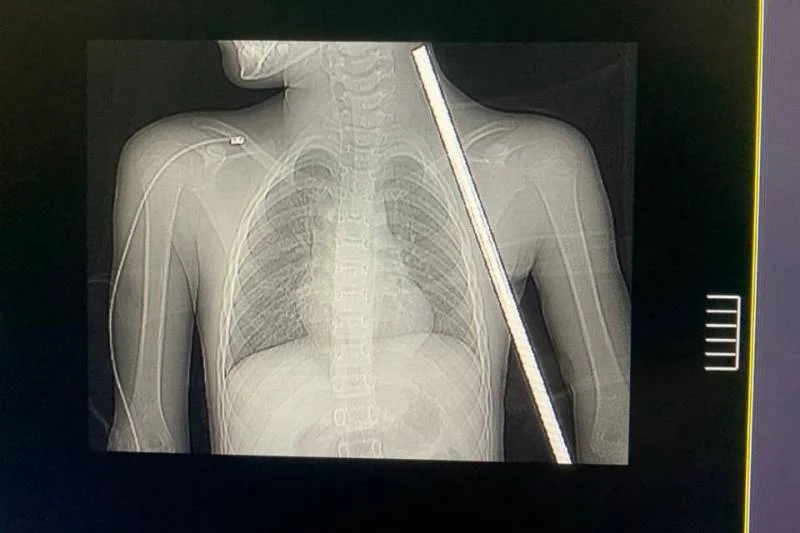

Foto: Reprodução |Um momento de descontração durante as férias quase se transformou em tragédia para Isabela da Conceição, de apenas 8 anos, no último dia 5 de janeiro, em Novo Progresso, no sudoeste do Pará. Enquanto brincava em uma mureta em um terreno baldio, Isabela sofreu um acidente impressionante: um vergalhão de ferro perfurou seu corpo, atravessando da região abaixo do tórax até próximo ao pescoço.

Segundo a neurocirurgiã Ingrid Soani, responsável pelo procedimento, o caso era extremamente delicado. “A perfuração passou muito perto de estruturas importantes, como nervos e vasos sanguíneos. Os riscos incluíam perda de movimentos nos braços, choque hipovolêmico por rompimento de vasos e infecções graves devido à ferrugem no vergalhão”, explicou.

Antes da cirurgia, a equipe médica realizou exames de imagem detalhados para mapear os danos e planejar a intervenção, minimizando possíveis complicações. A operação, que durou cerca de duas horas, foi conduzida com extremo cuidado.

Durante o procedimento, as áreas afetadas foram cuidadosamente abertas para a remoção do vergalhão sem causar novas lesões. “Felizmente, nenhuma estrutura vital foi comprometida, e conseguimos finalizar a cirurgia com sucesso”, afirmou a neurocirurgiã.